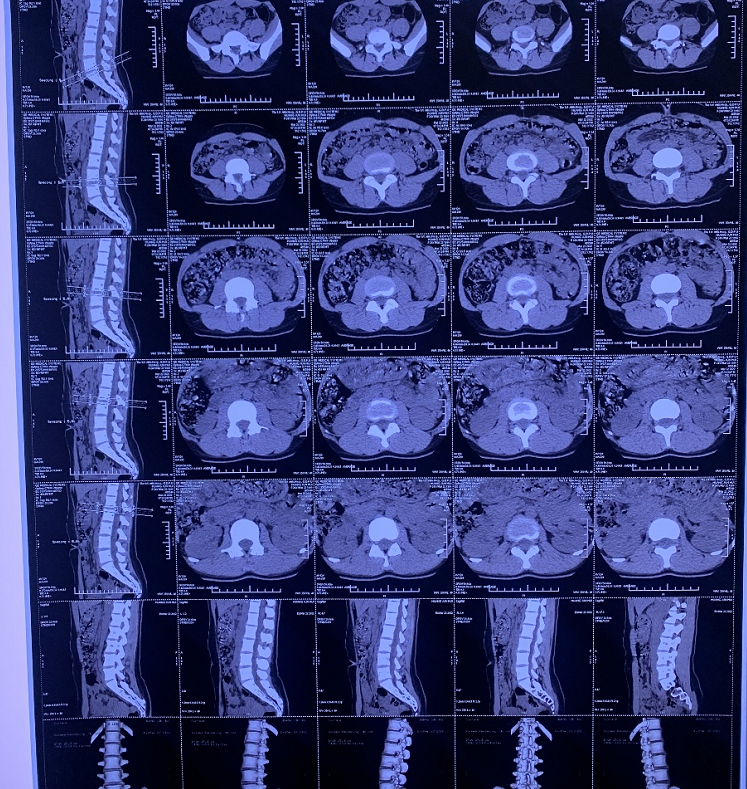

CT結果顯示:腰骶L5S1突出。這是指黃歡的第5腰椎和第1骶椎之間的椎間盤有變化,往外突出,有時會出現(xiàn)壓到神經(jīng)的狀態(tài)。

◎ 患者的CT檢查報告。/ 受訪者供圖